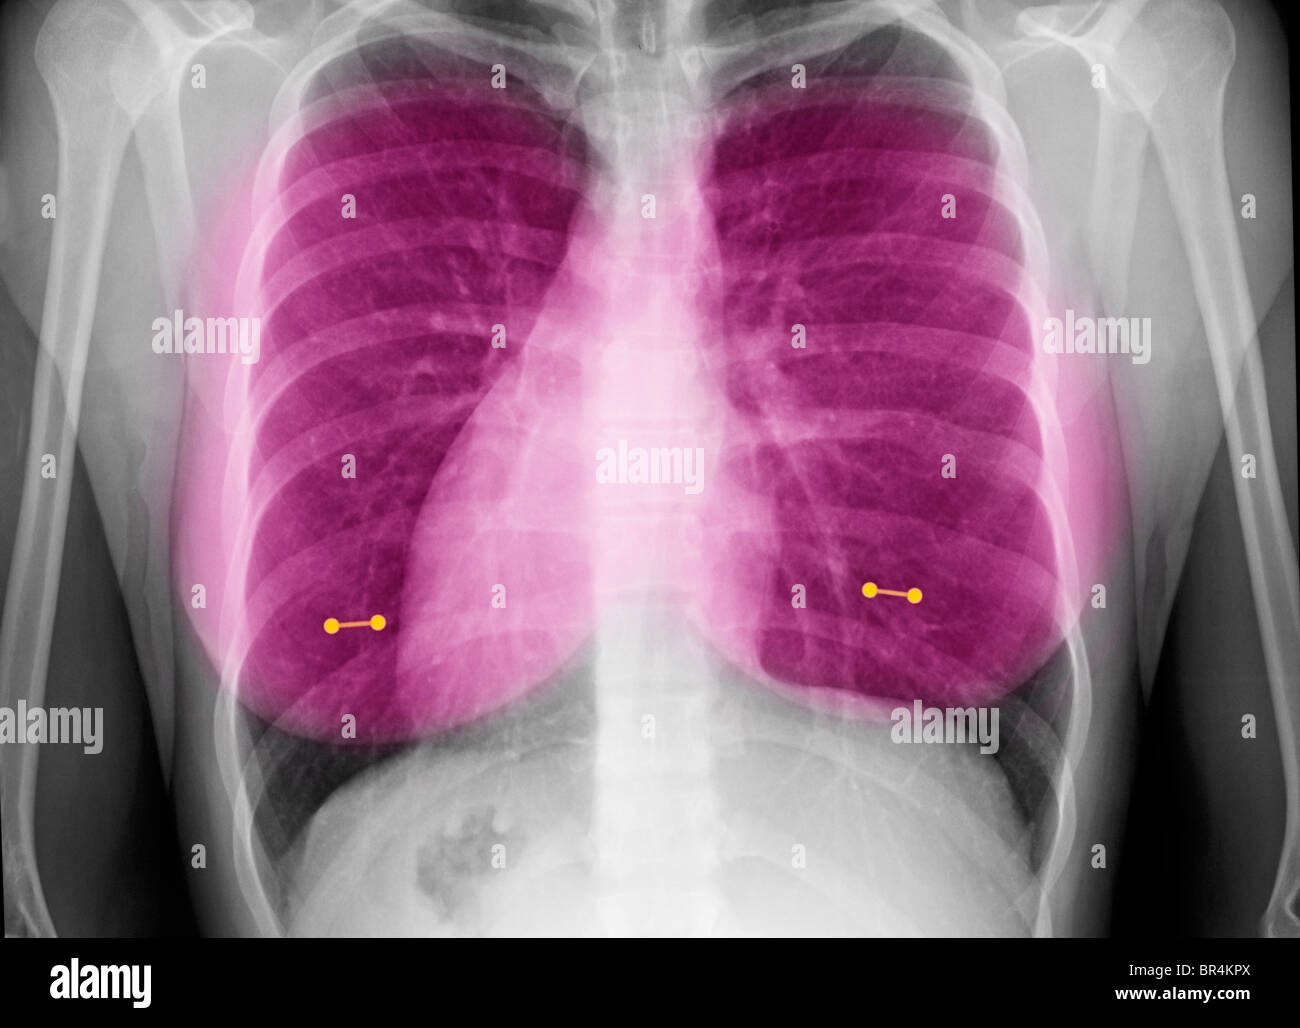

Nipple Piercing On X Ray . Also could be because of. So the artefacts caused by nipple piercing is less than belly piercing. This is near where the apex beat is best palpated and auscultated during clinical Generally for females, breasts are thicker than tummy. Nipple markers can be a useful technique in the evaluation of the nodular densities If the jewelry is covering a place of interest (e.g. It is common to see jewelry artifacts on imaging examinations, most commonly plain radiographs, although also on other modalities,. Case contributed by garth kruger.

Radiograph of the chest showing the piercing of the left nipple Nipple Piercing On X Ray So the artefacts caused by nipple piercing is less than belly piercing. If the jewelry is covering a place of interest (e.g. This is near where the apex beat is best palpated and auscultated during clinical Case contributed by garth kruger. Also could be because of. It is common to see jewelry artifacts on imaging examinations, most commonly plain radiographs,. Nipple Piercing On X Ray.